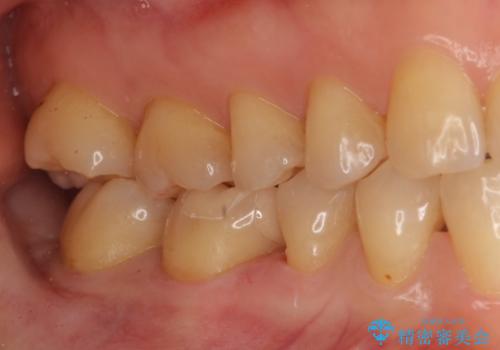

銀歯を白く セラミックインレーに

- 銀歯にしたのが20年以上前とのことで、白くやりかえたいということでした。

セラミックインレーにしています。

銀歯を外して、下に虫歯があればしっかり取ります。しみるなどの症状が出る前がおすすめです。